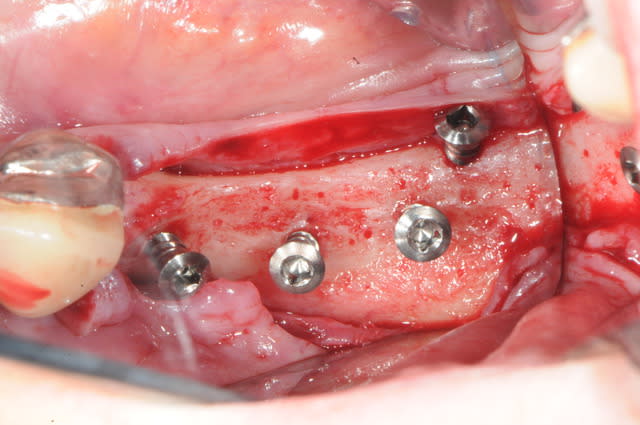

voici peut être une autre solution qui te satisfera d'avantage car beaucoup plus simple à mettre en œuvre.

c'est une simple ROG avec des vis pour maintenir l'espace sous la membrane.